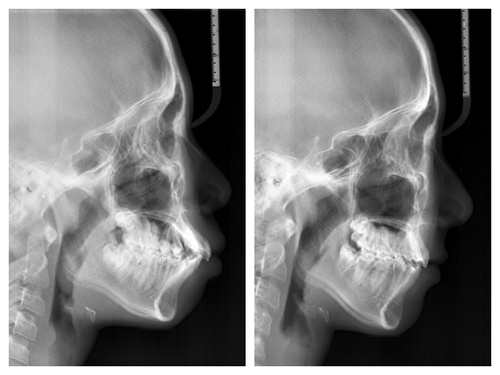

사실 골격적인 비대칭이 심해서 교정이 끝나도 비대칭이 남겠지만 돌출이 개선되면 훨씬 예뻐질것이기에 과감히 발치를 하고 좌,우 최대한 중심선을 맞추면서 교정을 끝낸 케이스

입이 들어가서 예뻐진 것 뿐아니라 사진을 찍으면 두드러지던 비대칭도 많이 줄어들었다.

돌출입 교정을 통해 입술의 모습이 많이 바뀌니 잇몸 노출량도 훨씬 줄어서 웃을때 신경이 더 쓰인다고...